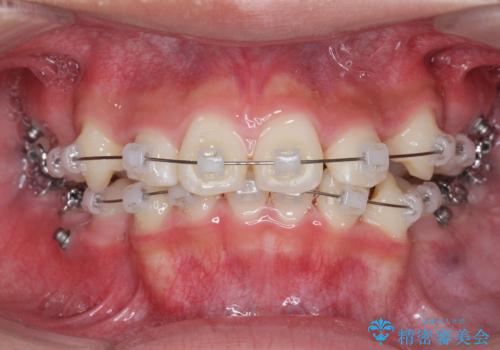

- 前歯のがたつきが原因で歯ブラシしづらい、見た目を改善したい!と矯正治療を希望され来院されました。

スペースの不足が見られるため、小臼歯の4本抜歯を行いマルチブラケットを用いた矯正治療を計画します。

噛み締めが強く、治療に時間がかかりましたが矯正治療の仕上がりに満足いただくことができました。